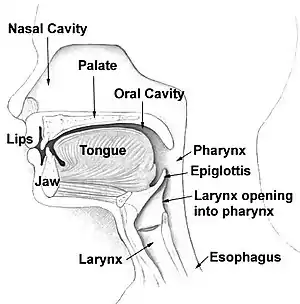

| Head and neck. Esophagus at bottom. | |